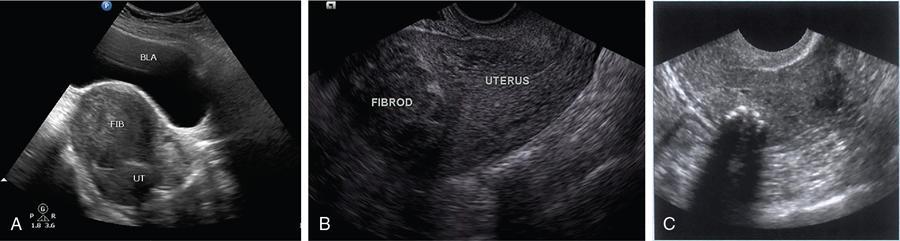

John De Lindsay, Sumathy, Vasumathy, Usha nandhini Ganeshan, N. Sundari ENDOMETRITIS Endometritis is defined as the inflammation of the uterine endometrial layer. Endometritis is frequently observed in the pregnant and postpartum population. Pelvic inflammatory disease (PID) and invasive gynaecological procedures are the most common causes of acute endometritis in nonobstetric population. Endometritis is the most complex asymptomatic and often presents with subclinical form of PID. Ultrasound may reveal minimal particulate endometrial fluid with mildly thickened endometrium showing increased vascularity. Computed tomography (CT) findings include a diffusely bulky uterus due by inflammation, mild fluid distension of endometrial cavity and striking endometrial enhancement in comparison to the adjacent myometrium due to mucosal hyperaemia. ‘Indistinct uterine border’ sign is observed in patients with endometritis, which is defined as the loss of distinction between the uterus and the adnexa. Since it is also observed in the cases of endometriosis or malignancy, it is a nonspecific sign. The age of the patient, clinical presentation, and the biopsy of endometrium helps in differentiating endometritis from other pathologies. UTERINE ARTERIOVENOUS MALFORMATION Uterine arteriovenous malformation (UAVM) is an abnormal connection between the arteries and the veins of the uterine myometrium without an intervening capillary bed. They were first reported by Dubreil and Loubat in 1926. They can be congenital or acquired. Even though UAVMs have varied presentation, uterine bleeding is the most common one. They often follow a pregnancy event. Episodic or occasionally torrential vaginal bleeding can occur. Congestive heart failure secondary to vascular steal can be a rare presentation due to a large UAVM. UAVM is most commonly an acquired condition. Pregnancy has a significant role in their pathogenesis. It is most commonly observed in reproductive age group. UAVMs are frequently observed in the postpartum period, few months after spontaneous miscarriage, surgical evacuation of uterus for miscarriage or medical termination of pregnancy. Infection, inflammation, retained products of conception (RPOC), gestational trophoblastic disease (GTD), gynaecologic malignancies, pelvic trauma and exposure to diethylstilboestrol can also lead to UAVMs. Few cases are also reported in young adolescent and postmenopausal females. UAVMs rarely are congenital and may be also associated with AVMs in other locations. Congenital AVMs Congenital AVMs have a central nidus with multiple feeding arteries and draining veins. In this condition, there is extension of the lesion beyond that uterus and multiple pelvic vessels other than uterine vessels draining into them. That cause of congenital AVMs are thought to be due to failure of embryological differentiation. With the progression of pregnancy, these vessels have the propensity to invade surrounding structures. Iatrogenic Acquired AVMs When the venous sinuses are incorporated into the scars of myometrium after the necrosis of chorionic villi, acquired malformations may arise. In contradiction to congenital AVMs, acquired AVMs multiple fistulous communication between the intramural arteries and the venous plexus. These AVMs may have either dual blood supply or a single supply from the uterine arteries and presents without nidus. Vaginal bleeding caused by pregnancy-related causes must be differentiated from UAVMs. Surgery/evacuation is the appropriate management for the former and the same is contraindicated in the UAVMs and hence an accurate definitive diagnosis is important. Grey-scale ultrasound findings are nonspecific and they are subtle heterogeneity of myometrium with multiple tubular or ‘spongy’ anechoic or hypoechoic areas. In spite of varied presentations such as an intramural uterine, endometrial or cervical mass-like lesions or prominent parametrial vessels, it has minimal mass effect. On colour Doppler, within the myometrium, a region of increased vascularity and most commonly with aliasing is seen. A group of vessels traversing the myometrium running perpendicular to and into the endometrium, from the arcuate vessels, can be seen. It is not specific, as they are also observed in RPOC, GTD, placental polyp and vascular endometrial neoplasm. In pulsed Doppler, multidirectional turbulent flow with intense vascularity can be seen with high peak velocity (mean peak systolic velocity [PSV] = 136 cm/s) and low resistance (mean resistance index = 0.3) flow. The arteries have low pulsatility while the draining veins are pulsatile and show high velocity flow. Magnetic resonance imaging (MRI) offers noninvasive confirmation of the diagnosis of UAVM. T1-weighted and T2-weighted images show multiple serpentine signal voids along the uterine wall, endometrial cavity and parametrium. Contrast-enhanced MR angiography shows intensely enhancing complex serpentine abnormal vessels with early venous return. Catheter angiography can be reserved only for women who require embolization of the AVM. The consent for both diagnostic angiography and therapeutic embolization should be obtained simultaneously to avoid repeat therapeutic procedures. Management of UAVM depends on: UAVM can be treated with medical therapy with hormones, uterine artery embolization or with definitive hysterectomy. Once the diagnosis of a UAVM is confirmed, the treatment option depends on the clinical condition of the patient. The size of the AVM bears no correlation to the need for embolization. Timmerman et al. found that AVMs having PSV of at or above 0.83 m/s, most often requires embolization. Also, the vascular malformation with PSV value below 0.39 m/s does not require embolization. Placental bed subinvolution, enhanced myometrial vascularity (EMV), molar pregnancy or RPOC are the other causes of uterine mass vascular malformations which usually has a mean PSV of 0.52 m/s and does not require embolization. Transcatheter targeted uterine artery embolization is indicated in selected cases, if bleeding persists to a degree that blood transfusions are required to maintain haemodynamic stability or multiple repeated acute hospitalizations. This is preferred over surgical management owing to its immediate minimally invasive and fertility sparing benefits. Gelfoam had been suggested earlier as the material of choice for embolization. Various other embolic materials like polyvinyl alcohol, Histoacryl glue, stainless steel coils, detachable balloons, and haemostatic gelatin are also used nowadays. Normal intrauterine pregnancies after embolization have been reported, proving that an adequate collateral blood supply can develop to support a full-term pregnancy. Gestational Trophoblastic Disease RPOC: Presence of endometrial pathology rather than myometrial origin. FIBROIDS Leiomyomas, also known as fibroids or myomas, are the most common gynaecologic neoplasms, occurring in 20%–30% of women of reproductive age. Symptomatic uterine fibroid accounts for about 30% of hysterectomies performed for women older than 18 years of age and 41% of hysterectomies performed for women from 44 to 64 years of age. Leiomyomas are the benign neoplasms made up of whorled fascicles of smooth muscle and fibrous connective attached to the uterine muscular wall. Even in the absence of true capsule, leiomyomas are well circumscribed and contains a pseudocapsule. Its size is variable, ranging from tiny microscopic to large tumours filling the abdomen. Most commonly, the uterine leiomyomas are seen in the myometrium of uterine corpus. However, it is also seen in the cervix (<5% of cases). On the basis of the location, uterine fibroids are classified as submucosal, intramural or subserosal. This classification is of clinical significance because the symptoms and treatment vary among these subtypes of leiomyomas. Submucosal myomas are further subclassified as 0, I and II depending on the percentage within the endometrial cavity. The first two categories can be removed hysteroscopically (Table 11.15.3.1). Pedunculated leiomyomas are attached to the uterus by a stalk and may be either intracavitary or exophytic (narrower than 50% of diameter of myoma). Rarely, a submucosal fibroid may grow pedunculated and extends into the cervical canal or vaginal canal and its prevalence is about 2.5%. Pedunculated subserosal leiomyomas may undergo torsion, resulting in infarction accompanied by pain. Lateral growth into broad ligament leads to intraligamentous leiomyoma (Table 11.15.3.1). Rarely, a pedunculated leiomyoma may become detached from the uterus (parasitic leiomyoma). Depending on the location, size and number of uterine fibroids, it has varied presentation. Symptoms caused by leiomyomas are classified into three different categories such as abnormal uterine bleeding, pelvic pressure and pain and reproductive dysfunction. Submucosal leiomyomas and intramural leiomyomas are often associated with menorrhagia (Table 11.15.3.1). Because of leiomyoma, uterus may be irregularly shaped and causes symptoms based on their locations. Anterior leiomyomas cause urinary symptoms, whereas the posterior leiomyomas cause constipation. Ureter may be compressed by broad ligament leiomyomas and presents as hydroureter or hydronephrosis. In case of degeneration or torsion of a pedunculated leiomyoma, acute pain may be the presentation. Leiomyomas are an infrequent primary cause of infertility. Malpresentation, pregnancy failures and dystocia are reported. Ultrasound is the first-line imaging modality because it is a cost-effective portable real-time examination that provides good anatomic detail. Leiomyomas appear as a well-defined round or oval hypoechoic solid mass. It is mostly associated with posterior shadowing possibly due to calcifications or interface of the margins of the leiomyoma with the normal myometrium. Degeneration or lipoleiomyoma can be suggested when there is internal echo-poor or hyperechoic foci, respectively. The presence of hypervascularity in a large solitary uterine mass can identify suspicious masses, such as a leiomyosarcoma (LMS). Another study found that there is an increased detection rate of uterine sarcomas while using a cut-off value of 41 cm/s. In the assessment of a uterus enlarged with multiple leiomyomas, ultrasound has FOV limitations. Likewise, it has limited role in the assessment of retroverted uteri, pedunculated subserosal myomas and concomitant adnexal processes. Little has been reported regarding sonographic changes after MR HIFU and uterine fibroid embolization (UFE). Differential diagnosis has been discussed in Table 11.15.3.2. Hyperechoic unlike a myomatous polyp which appears hypoechoic Heterogeneous endometrium with little mass effect Enlarged uterus and a deformed contour are the most common computed tomography (CT) findings. Even though CT is the primary modality for the staging of cancers, it has limitation of reduced contrast resolution for the assessment of focal myometrial masses, and associated with risk of ionizing radiation. Also, in delineating the zonal anatomy for accurate localization of leiomyomas and LMSs, CT is inferior to magnetic resonance imaging (MRI). More often dense or amorphous calcification is seen. Almost exclusively, on plain radiography or CT, these patterns of calcification favours the diagnosis of leiomyoma. Ring-like calcification at the margins of a leiomyoma is a rarely observed pattern, which represents the thrombosed veins. Positron emission tomography (PET)/CT is an ideal modality for the confirmation of malignancy and also helps in detection of metastasis and recurrence. In a small study of patients with histopathologically confirmed uterine sarcoma found that on comparing with the findings of MRI and ultrasound with power Doppler imaging, the results of fluorodeoxyglucose (FDG) PET examinations were 100% positive. However, it has limitations such as increased false-positive rate and reduced widespread availability. MRI appearance of leiomyomas: MRI is considered as the most accurate imaging technique for the detection and localization of leiomyomas. In determining the presence and location of leiomyomas in infertile women before myomectomy, MRI has been shown to be more accurate and sensitive than US or hysterosalpingography. Nondegenerated uterine leiomyomas usually has a typical MRI appearance of (Table 11.15.3.4) well-circumscribed masses with homogeneously decreased T2-weighted signal intensity. TABLE 11.15.3.3 Note: SI, signal intensity; ADC, apparent diffusion coefficient. Compared with that of normal smooth muscle myometrium. Degenerated leiomyomas have varied imaging appearances on T1-weighted, T2-weighted and contrast-enhanced images as described in Tables 11.15.3.4 and 11.15.3.5. Hyaline Oedema *Common *50% cases *Usually peripheral Cystic Myxoid Carneous, red, or UAE associated Calcific Leiomyoma variants (Tables 11.15.3.4 and 11.15.3.6): There are several, such as mitotically active, cellular and atypical leiomyomas, as well as smooth muscle tumours of uncertain malignant potential (STUMP). On histopathological examination, the nondegenerated fibroids are made up of goals of uniform smooth muscles with varied amounts of collagen. Cellular leiomyomas, which are composed of compact smooth muscles cells only with no collagen, will demonstrate increased T2-weighted signal intensity and homogeneous enhancement. There is a greater risk of recurrence in case of atypical leiomyomas and uterine STUMP. The patients who had undergone myomectomy and were found to have atypical leiomyoma, must be under surveillance with an annual pelvic ultrasound or MRI. Since the recurrences may presents as pelvic or abdominal masses or as pulmonary metastases, for all the patients with STUMP lesions, routine physical examinations, including pelvic examinations and the baseline CT of the chest, abdomen and the pelvis are recommended for every 6 months for 5 years and then annually thereafter. In addition, prompt re-exploration and staging is recommended for patients with STUMP who have undergone a morcellation myomectomy. An aggressive imaging surveillance is considered, when the disease is present. Atypical leiomyomas and STUMPs routinely express progestin receptors; however, because of the low recurrence rates, there is no role for adjuvant hormonal therapy. Atypical uterine masses can be treated surgically with hysterectomy or myomectomy. Histologic subtype Cellular leiomyoma Round or oval Single large lesion with absence of coexistent adenomyosis Responds to GnRH analogues Cured with surgery No need for follow-up Lipoleiomyoma Well defined: round or oval STUMP Round or oval Intense surveillance Note: SI, signal intensity; ADC, apparent diffusion coefficient; UAE, uterine artery embolization; STUMP, smooth muscle tumours of uncertain malignant potential. Being a benign neoplasm, fibroids usually have a pushing border and rounded edges. But, specific types of fibroids represent growth pattern variations, such as intravenous leiomyomatosis, metastasizing leiomyoma, diffuse leiomyomatosis and peritoneal disseminated leiomyomatosis. Retroperitoneal growth and parasitic growth are the other atypical growth patterns. Even cervical and vaginal leiomyomas may show growth pattern. It is important to note that adenomyosis and focal myometrial contraction can coexist and distinction is important at preprocedure imaging (Table 11.15.3.7).